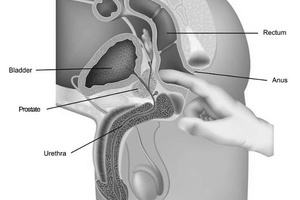

Простатит – широко распространенное заболевание, которому подвержены все возрастные группы. Это воспалительный процесс физиологической либо инфекционной природы, локализующийся в ткани предстательной железы.

Если не принять своевременных мер, болезнь начинает прогрессировать. Предстательная железа функционирует, вырабатывая секрет, в котором активно размножаются болезнетворные микробы. Картина заболевания усугубляется особым строением простаты.

В толще этой железы нет крупных кровеносных сосудов, поэтому кровоснабжение органа затруднено. Это способствует накоплению в ткани простаты продуктов жизнедеятельности болезнетворных микробов и провоцирует застойные явления.